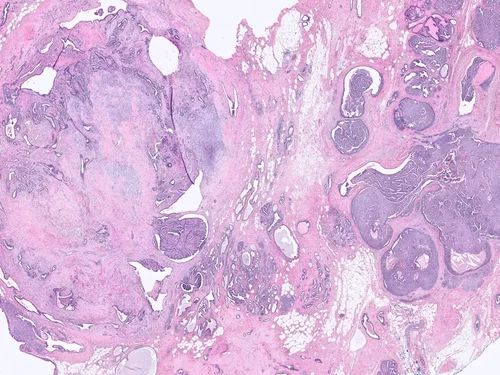

Benign Phyllodes Tumor

Phyllodes tumors are uncommon biphasic lesions that account for <1% of breast tumors. They generally occur in older women as compared to fibroadenomas, and often the patients have a history of a rapidly enlarging tumor. They tend to be larger than fibroadenomas, although this is not a hard and fast rule.

Histologically, phyllodes tumors are characterized by stromal hypercellularity and prominent intracanalicular growth pattern, sometimes with branching, cleft-like spaces.

Malignant Phyllodes Tumor

Frond-like projections of cellular stroma covered by epithelium and myopeithelium protruding into epithelial-lined cystic spaces create a leaf-like appearance.